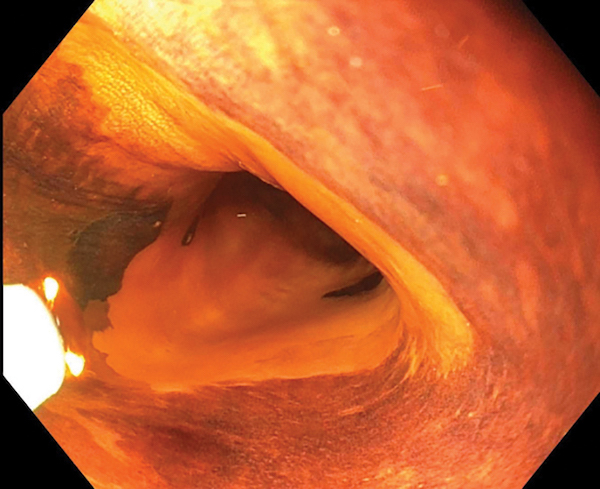

A 68-year-old woman is referred to your practice for a history of squamous high-grade intraepithelial neoplasia (HGIN). Staining of the mucosa with 1.5% Lugol’s iodine yields the appearance in the figure. You would like to arrange treatment with the highest long-term probability of success and minimization of complications. The patient is very worried about the potential for stricturing and asks you to do all that you can to minimize this risk. What do you recommend next?

The lesion above shows a 4-cm circumferential non-staining area. Endoscopic mucosal resection of such a long, circumferential area of squamous neoplasia has a high risk of stricturing. After staining with Lugol’s iodine, it is the non-staining, not the staining areas, which are likely to be neoplastic. RFA of this lesion results in complete eradication of neoplasia in >80% of patients in most studies. Ablation for squamous epithelium can be successfully performed at energy densities lower than that used for columnar epithelium, to reduce the risk of stricturing.